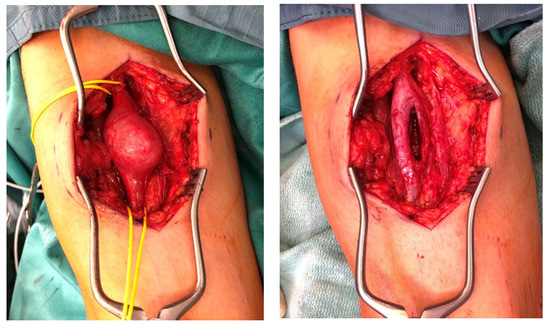

Giant Atypical Neurofibroma of the Calf in Neurofibromatosis Type 1: Case Report and Literature Review

Background and Clinical Significance: Neurofibromatosis type 1 (NF1) predisposes individuals to various peripheral nerve sheath tumors (PNSTs), including benign neurofibromas, malignant peripheral nerve sheath tumors (MPNSTs), and intermediate lesions known as atypical neurofibromatous neoplasms of uncertain biologic potential (ANNUBP), previously often termed atypical neurofibroma. These atypical lesions are considered premalignant precursors to MPNST. Case Presentation: We present the case of a 33-year-old male with NF1 who developed a rapidly growing, painful mass in his right calf. Clinical examination revealed signs consistent with NF1. Magnetic resonance imaging showed a large, heterogeneous mass in the lateral compartment. Biopsy revealed a neurofibroma with hypercellularity, moderate atypia, scarce S100 positivity, focal CD34 positivity, and an elevated Ki-67 proliferation index of 10–12%, consistent with ANNUBP. The patient underwent wide surgical resection, including the fibula and peroneal muscles. At the 30-month follow-up, there was no local recurrence, though the patient had a mild residual limp. Discussion: This case highlights the clinical presentation, diagnostic features, and management considerations for ANNUBP in NF1, emphasizing the importance of recognizing warning signs and the role of pathology in guiding treatment for these high-risk precursor lesions. Full article